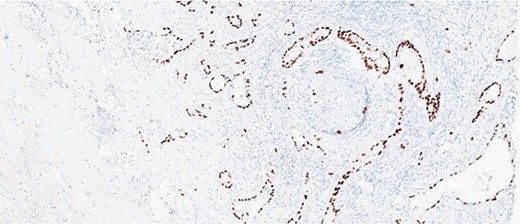

Histological evaluation revealed a 2.7 cm moderately differentiated ASC with extensive necrosis (Fig. 2), perimuscular connective tissue invasion, and lymphovascular involvement. Immunohistochemistry was positive for p40, confirming squamous differentiation (Fig. 3). All surgical margins were uninvolved, and three examined lymph nodes were negative. The tumour was staged as pT2aN0 based on the American Joint Committee on Cancer (AJCC) 8th edition criteria [11].

Immunohistochemical stain is positive for p40, highlighting squamous differentiation.